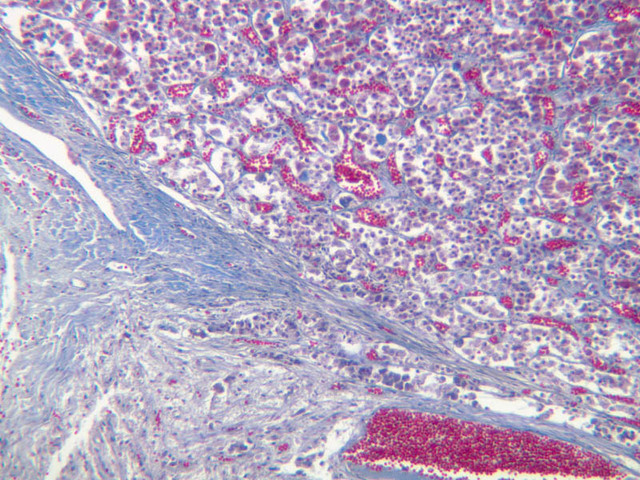

The adrenal gland (slide B-59, H&E [2.5x-labeled, 10x-labeled, 20x, 40x-labeled] [2.5x, 10x-labeled, 20x, 40x]; B-60, H&E [2.5x-labeled, 10x, 20x, 40x]; B-62, H&E [10x, 20x, 40x] [2.5x, 10x]) is a composite organ consisting of two functionally, structurally and embryologically different parts—an outer cortex and an inner medulla. Observe the gland at low power. Find the loosely organized tissue that comprises the medulla and the partially-separated columns of cells that make up the cortex. Scan the capsule and the tissue around it, looking for nerves and blood vessels. Study the pattern of cortical vasculature. In a pattern similar to that seen in the pars distalis of the pituitary, sinusoids run along the edges of columns or cords of cells. Owing to different arrangements of its constituent cells, the adrenal cortex has a layered appearance. From the capsule inward, these cortical layers are known as the zona glomerulosa, the zona fasciculata, and the zona reticularis.

The zona glomerulosa is located immediately beneath the capsule (B-60 adrenal gland, dog [10x, 20x] [20x, 40x]; B-59 [2.5x, 10x, 20x] [2.5x, 10x, 20x]). Its constituent cells are arranged in arcs or spheres, and, owing to their relatively small size, their nuclei appear to be close together. Cells of the zona glomerulosa secrete mineralocorticoids (e.g., aldosterone). The zona fasciculata consists of parallel columns or cords of cells that radiate toward the medulla and are separated by blood sinusoids (B-60 [2.5x, 10x, 20x, 40x]; B-62 [20x, 40x]). Owing to the extraction of lipids during histological processing, the cytoplasm of cells in the zona fasciculata appears highly vacuolated or "foamy". Cells of the zona fasciculata secrete glucocorticoids (e.g., hydrocortisone & cortisone) and some gonadocorticoids (weak androgens). The zona reticularis is the deepest cortical layer and lies adjacent to the medulla (B-60 [20x, 40x]; B-62 [20x, 40x]). It is characterized by irregular, interconnecting cords of cells which are separated by anastomosing capillary networks or sinusoids. Cells of the zona reticularis, which are smaller than those of zona fasciculata and do not contain as many lipid vacuoles, secrete gonadocorticoids and some glucocorticoids.